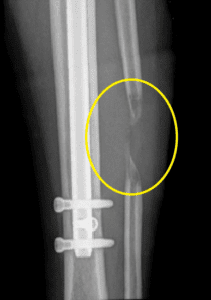

患者在外部设施中延长后出现间歇愈合

该患者在外部设施中身材延长了厘米。完成延长手术几个月后,腓骨的间歇愈合很小。